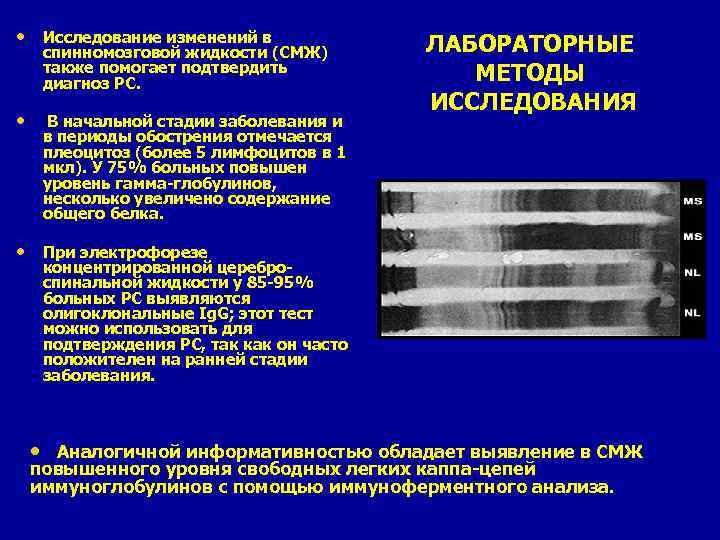

• Исследование изменений в спинномозговой жидкости (СМЖ) также помогает подтвердить диагноз PC. • В начальной стадии заболевания и ЛАБОРАТОРНЫЕ МЕТОДЫ ИССЛЕДОВАНИЯ в периоды обострения отмечается плеоцитоз (более 5 лимфоцитов в 1 мкл). У 75% больных повышен уровень гамма-глобулинов, несколько увеличено содержание общего белка. • При электрофорезе концентрированной цереброспинальной жидкости у 85 -95% больных PC выявляются олигоклональные Ig. G; этот тест можно использовать для подтверждения PC, так как он часто положителен на ранней стадии заболевания. • Аналогичной информативностью обладает выявление в СМЖ повышенного уровня свободных легких каппа-цепей иммуноглобулинов с помощью иммуноферментного анализа.